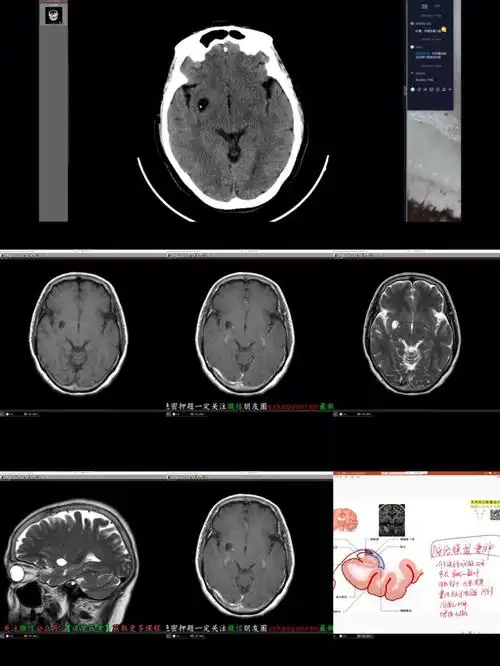

规培生活之脑膜瘤&脉络膜裂囊肿